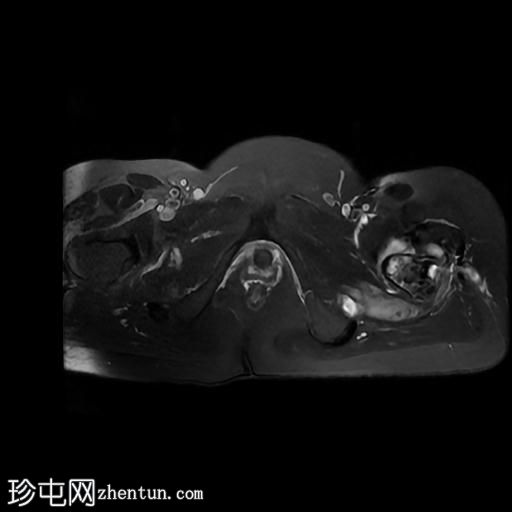

MRI

轴位

T2加权像

左髋关节存在严重的关节病变,表现为关节间隙显著变窄、软骨丢失、软骨下骨髓水肿以及囊性改变。

此外,左股骨颈基底部、股骨粗隆间区及股骨大转子区域可见骨髓信号异常及皮质破坏。伴有滑膜增厚及较大的冷脓肿腔,提示左股骨颈及股骨粗隆间区骨髓炎。

另一处较大的冷脓肿从股骨受损部位开始向上延伸至左侧臀肌。

在左侧股骨外侧皮下可见低信号窦道。